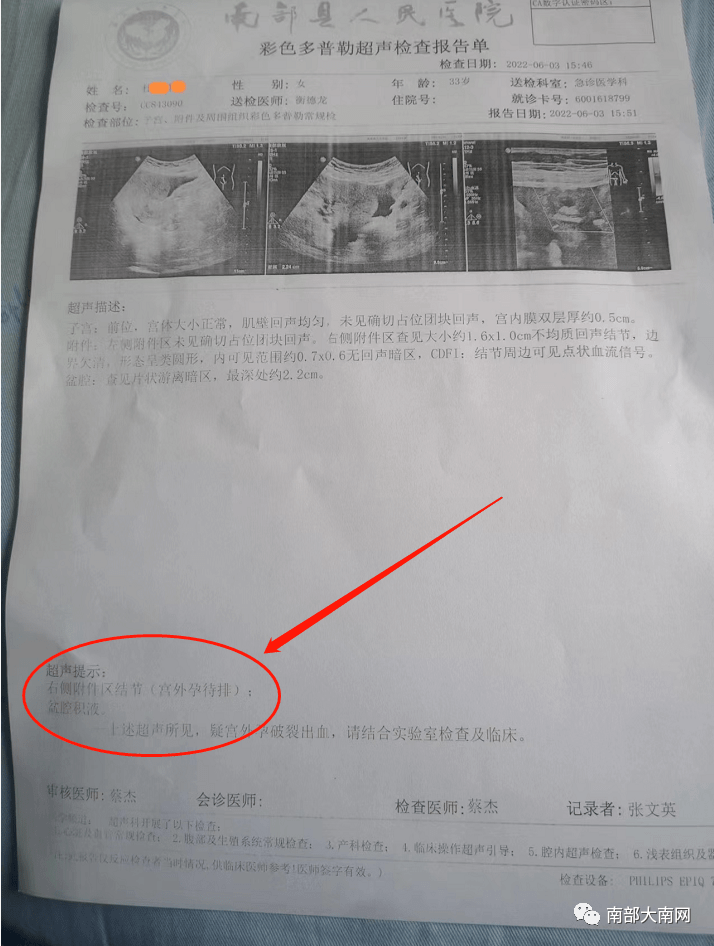

宫外孕当急性阑尾炎手术南部县人民医院最新回复

图片尺寸714x946